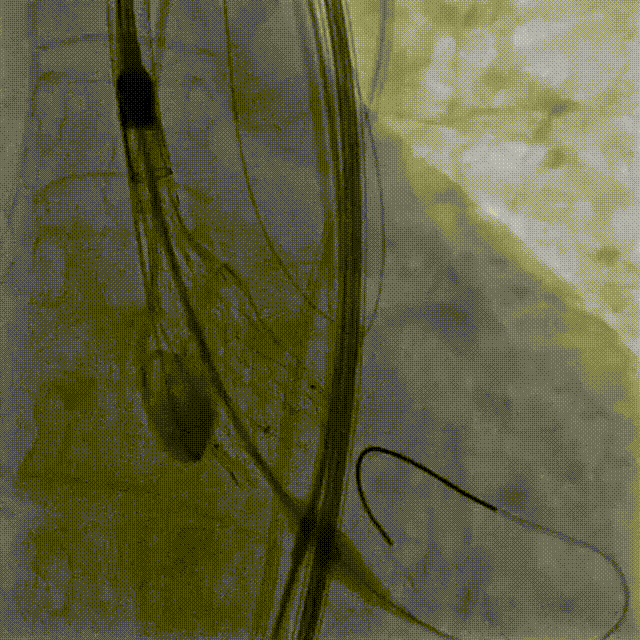

TriGUARD3™抗栓塞远端脑保护装置在介入瓣膜释放完成后撤出,术中未出现任何并发症。

VenusA-Valve完成释放

TriGUARD3™脑保护装置作为第一个进入人体,最后一个撤出,离开人体的器械。有效阻挡整个TAVR手术过程中栓塞物质进入脑部,从而避免新发大面积脑梗塞病灶产生,降低脑卒中的发生率。

术后被取出的TriGUARD3™脑保护装置